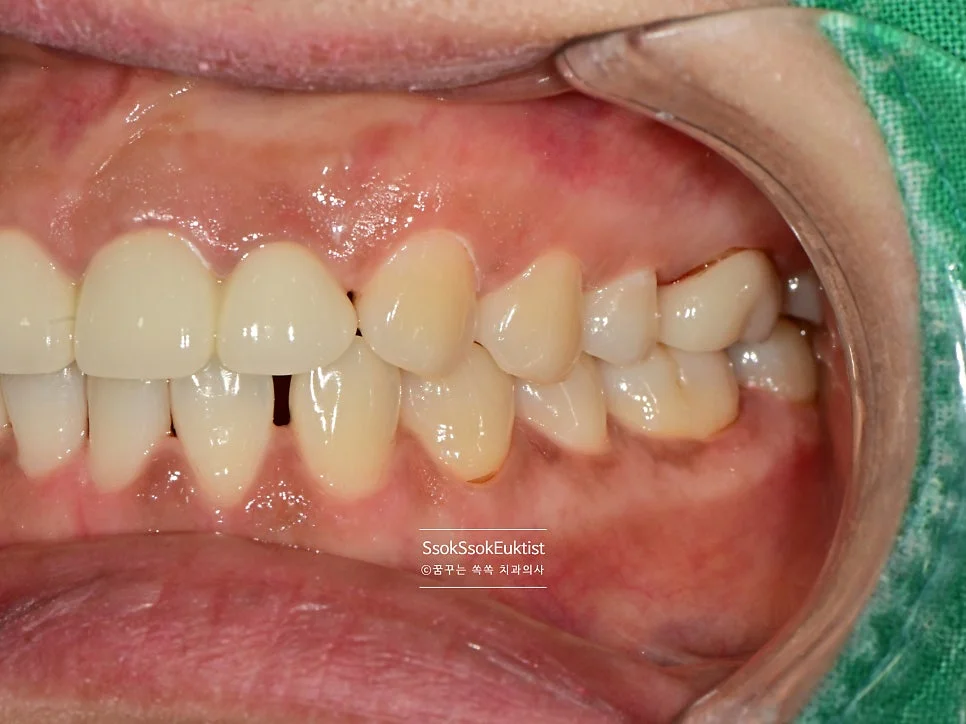

수면 스케일링 전후 비교 구강 사진

수면 스케일링 전후 비교

스케일링 전 구강 정면 임상 사진

구강 정면 — 관리가 조금 필요해 보이지만…

이 증례에서도 사진을 보면 구강 내 관리가 조금 필요해 보입니다만,